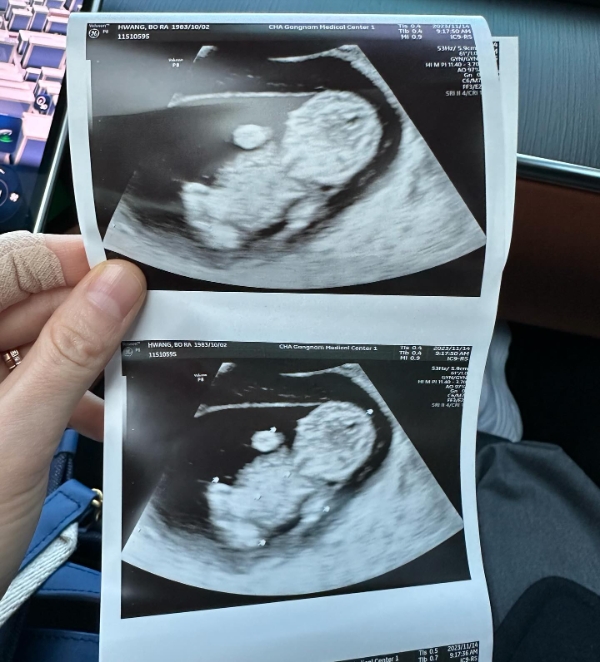

황보라는 지난 19일 자신의 인스타그램에 "결혼한 지 딱 일 년이 되었는데 저희 부부에게 하나님께서 아기천사를 주셨다"며 아기 초음파 사진을 공개했다.

황보라는 같은 날 자신의 유튜브 채널에 올린 영상에서 시험관 시술을 했다고 고백했다. 영상에서 황보라는 "제가 시험관을 1년 정도 했다. 안 해본 사람은 이 고통을 모른다. (시험관 시술을) 4차까지 했는데, 공부를 정말 열심히 했다. 이 모든 것들을 좀 쉽게 풀려고 한다"라며 새로운 유튜브 콘텐츠를 예고했다.

두 사람은 결혼식 약 한 달 전 SBS 예능 프로그램 '동상이몽2'에 동반 출연해 2세 준비를 위해 결혼식보다 혼인신고를 먼저 올렸다고 밝혔다. 당시 황보라는 "마흔이라 아이 생각에 혹시나 해서 병원에 갔었는데 결과가 안 좋게 나오더라"며 "시험관 등 시술을 하려면 혼인신고가 돼 있어야 했다"고 설명했다.